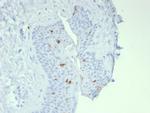

Langerin/CD207 (Marker of Langerhans Cells) Antibody (50489-MSM11-P1ABX) in IHC (P)

Formalin-fixed, paraffin-embedded human skin stained with Langerin Mouse Monoclonal Antibody (LGRN/7541). HIER: Tris/EDTA, pH9.0, 45 min. 2 °: HRP-polymer, 30 min. DAB, 5 min. {{ $ctrl.currentElement.advancedVerification.fullName }} 验证信息 View more